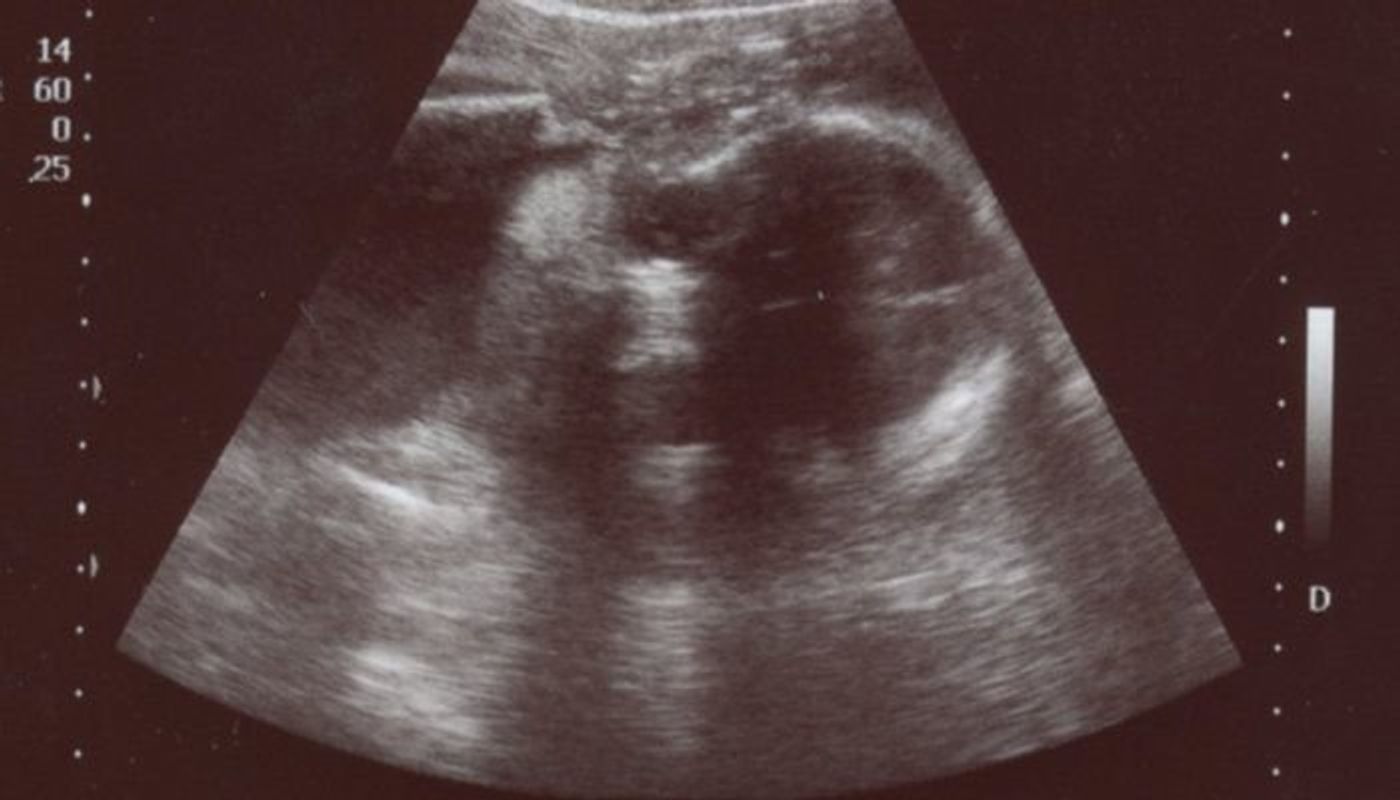

産まれた直後と妊娠28週目のエコー写真の比較です。 左:産まれた直後 右:妊娠28週目 このような写真が枚、それ以外に約8分間の動画をDVDで貰えました。超音波 (エコー) 検査で胎児の頭部や腹部、大腿骨などを計測します。こ れを胎児計測と呼んでいます。 推定児体重:胎児計測の結果から推定児体重(EFW estimated fetal weight) を計算することができます。胎児は妊娠の進行とともに成長します。発育の具 合を評価するためには、妊娠週数ごとに(06年 胎児心エコーガイドライン作成委員会編) •胎児心臓スクリーニング(レベルⅠ) –原則としてすべての妊婦が対象 •胎児心精査(レベルⅡ) –診断確定のために胎児心疾患に精通した医師が 精密

妊娠10週の胎児の体重や母体の様子看護師が解説 18年5月27日 妊娠3ヶ月のエコー写真の様子 妊娠6週頃の赤ちゃんはとても小さくエコーではわかりにくく、心拍はまだ確認できません。 まだ胎盤ができてないので卵黄嚢から栄養をもらっています。 妊娠3いる.胎児活動性はHypoxiaにより著明に減少する.母体による胎動記録法の中で最も 普及しているのは,Pearsonらのcounttoten胎動表であり,妊婦は午前9時より胎 (4)クリニカルカンファレンス(2);胎児評価を考える 2)エコーによる胎児機能評価妊娠28週(妊娠8ヶ月)のエコー写真・超音波写真 妊娠28週目:受精から1~1日目 胎児の大きさ:頭殿長(座高)が39~40cm 胎児の体重:1000~1300gほど 母体の変化:頻繁なお腹の張り・頻尿・血圧の上昇 妊娠28週(28w)に入ると、胎児の身長が伸びるペースはこれまでと比べると、ちょっとスローペースに。 皮下脂肪がついて丸みを帯び、皮膚のしわがなくなって

妊娠中期 後期の超音波検査 妊娠中の検査シリーズ おむつのムーニー 公式 ユニ チャーム